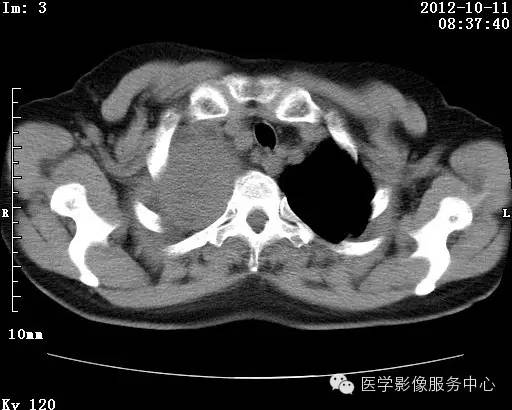

【病例】右肺巨大错构瘤1例CT影像表现

病史:女 65岁咳嗽咳痰 右肺巨大肿块就诊。

错构瘤的发病年龄多数在40岁以上,男性多于女性。 绝大多数错构瘤(约80%以上)生长在肺的周边部,紧贴于肺的脏层胸膜之下,有时突出于肺表面。其特征钙化为爆米花样钙化,内有脂肪软骨成分等等。最常见的部位是胸膜下肺实质内,其次为主支气管或肺叶、肺段支气管内。

理论上肺错构瘤为良性肿瘤,其结节形态、边界、与胸膜关系、与肺门关系、淋巴结肿大及与血管关系均应符合良性肿瘤的特点。